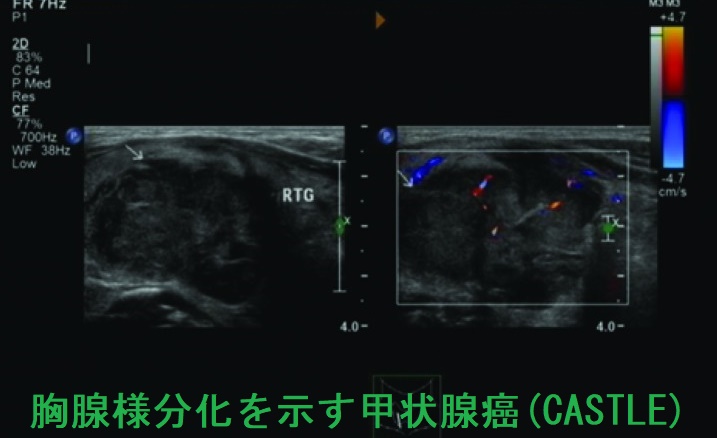

甲状腺の胸腺様分化を示す癌(CASTLE)の超音波(エコー)画像は、甲状腺悪性リンパ腫、甲状腺未分化癌、甲状腺原発扁平上皮癌と鑑別難で、辺縁不整・境界不明瞭、内部は不均一の低エコー結節(あるいは領域)。[Oncol Lett. 2016 Feb;11(2):1321-1326.]